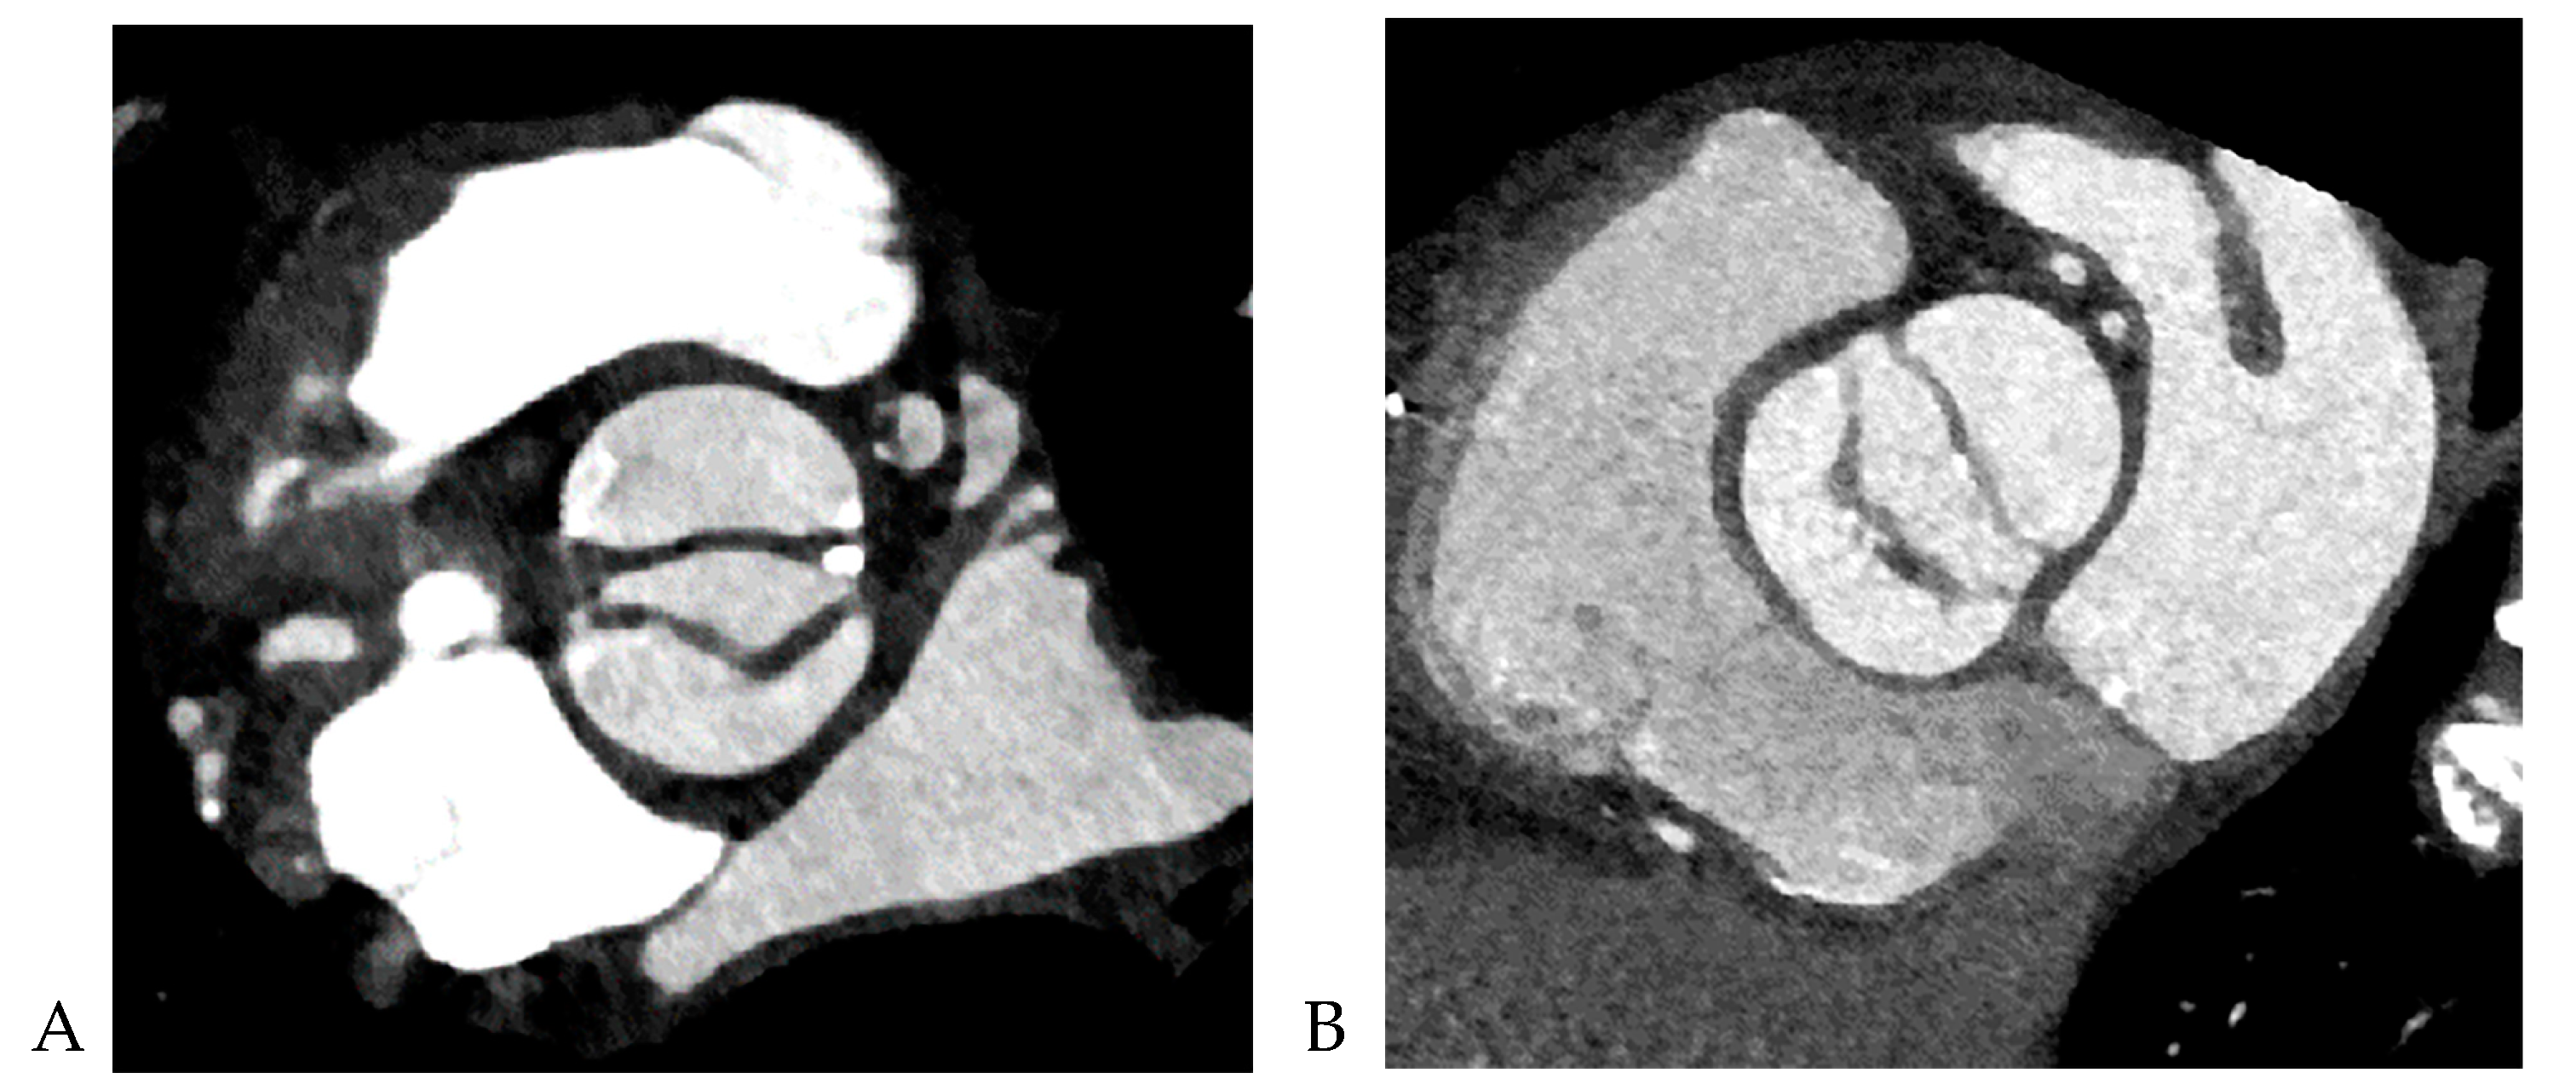

All CCT images were reviewed by a consensus of two radiologists with 16 and 5 years of experience, respectively, who were blinded to the clinical and surgical data. BAV was defined as the presence of two cusps and commissures in both systole and diastole. The following morphological variables were assessed: (1) presence or absence of raphe and (2) ascending aortic diameter. The term “raphe” defines the conjoined or “fused” area of two adjacent undeveloped leaflets that turn into a malformed commissure between both leaflets [9]. BAV morphology was classified as raphe+ or raphe- according to the presence or absence of raphe (Figure 1) [10]. The dimensions of the ascending aorta were measured at the sinus of Valsalva and tubular portion. Double-oblique coronal images of the ascending aorta were reconstructed at 10 % or 20 % of the cardiac cycle (early to mid-systole) to measure the tubular portion of the ascending aorta dimensions. The measurement of the maximum dimension of the aortic sinuses of Valsalva was performed using a double oblique transverse view of the aortic root at 10 % or 20 % of the cardiac cycle (Figure 2). Aortopathy refers to progressive dilatation of the ascending aorta and is defined as indexed maximal aortic diameter exceeding 21 mm/m2 of the body surface area (BSA) [11]. Ascending aortic dilation configurations were slightly modified from the Fazel classification, which was assigned to four types depending on whether the segment of the vessel was exclusively or predominantly involved in dilatation: normal aorta, type 1, isolated dilation of the ascending aorta root at the level of the sinus of Valsalva [12]; type 2, middle ascending dilatation at the level of the tubular ascending portion; and type 3, combined dilatation of the aortic root and mid-ascending aorta (Figure 3) [12]. Aortic aneurysms are defined as those with dimensions greater than 50 mm. The association between the presence of raphe and the risk of aortic valve dysfunction and aortopathy was also analyzed.

Figure 2. Example of measurement of the aortic dimensions at different locations. Oblique sagittal reformatted CT image shows sinus of Valsalva and tubular portion of ascending aorta at mid-systole (A). The maximum dimension of the tubular portion of ascending aorta was measured in a double oblique transverse view (B) obtained perpendicular to the aortic lumen (C and D) because the axial measurement exceeds the true measurement perpendicular to the long axis of the ascending aorta. The maximal aortic root dimension was measured sinus to sinus in bicuspid aortic valve with raphe (E) in a double oblique transverse view obtained perpendicular to the aortic sinus of Valsalva (F and G).